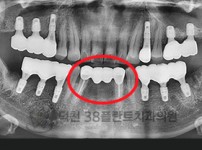

치료전후